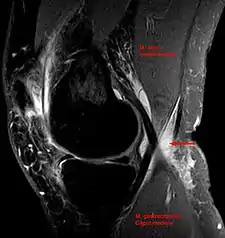

In adults, Baker's cysts usually arise from almost any form of knee arthritis (e.g., rheumatoid arthritis) or cartilage (particularly a meniscus) tear. Baker's cysts in children do not point to underlying joint disease. Baker's cysts arise between the tendons of the medial head of the gastrocnemius and the semimembranosus muscles. They are posterior to the medial femoral condyle.

Risk factors include other knee problems such as osteoarthritis, meniscal tears, or rheumatoid arthritis.[1][3][4] The underlying mechanism involves the flow of synovial fluid from the knee joint to the gastrocnemio-semimembranosus bursa, resulting in its expansion.[1] The diagnosis may be confirmed with ultrasound or magnetic resonance imaging (MRI).[3]

Diagnosis is by examination. A Baker's cyst is easier to see from behind with the patient standing with knees fully extended. It is most easily palpated (felt) with the knee partially flexed. Diagnosis is confirmed by ultrasonography, although if needed and there is no suspicion of a popliteal artery aneurysm then aspiration of synovial fluid from the cyst may be undertaken with care. An MRI image can reveal presence of a Baker's cyst.